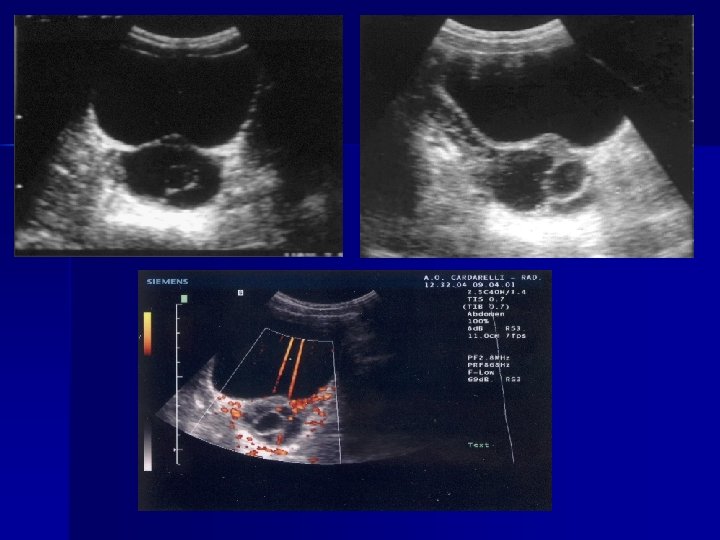

ECOGRAFIA E’ l’esame più utilizzabile nella patologia addominale Possiede: elevata specificità(91 -96%) valore predittivo più elevato versus esame clinico(88>69%).

Ecografia n n E’ una tecnica accurata nell’evidenziare : infiammazioni peri-appendicolari, ileite terminale, adenite mesenterica. invaginazione intestinale patologia testicolare e ginecologica Il limite di questa tecnica è che la qualità della lettura è molto legata alla capacità ed all’esperienza dell’operatore

Colelitiasi